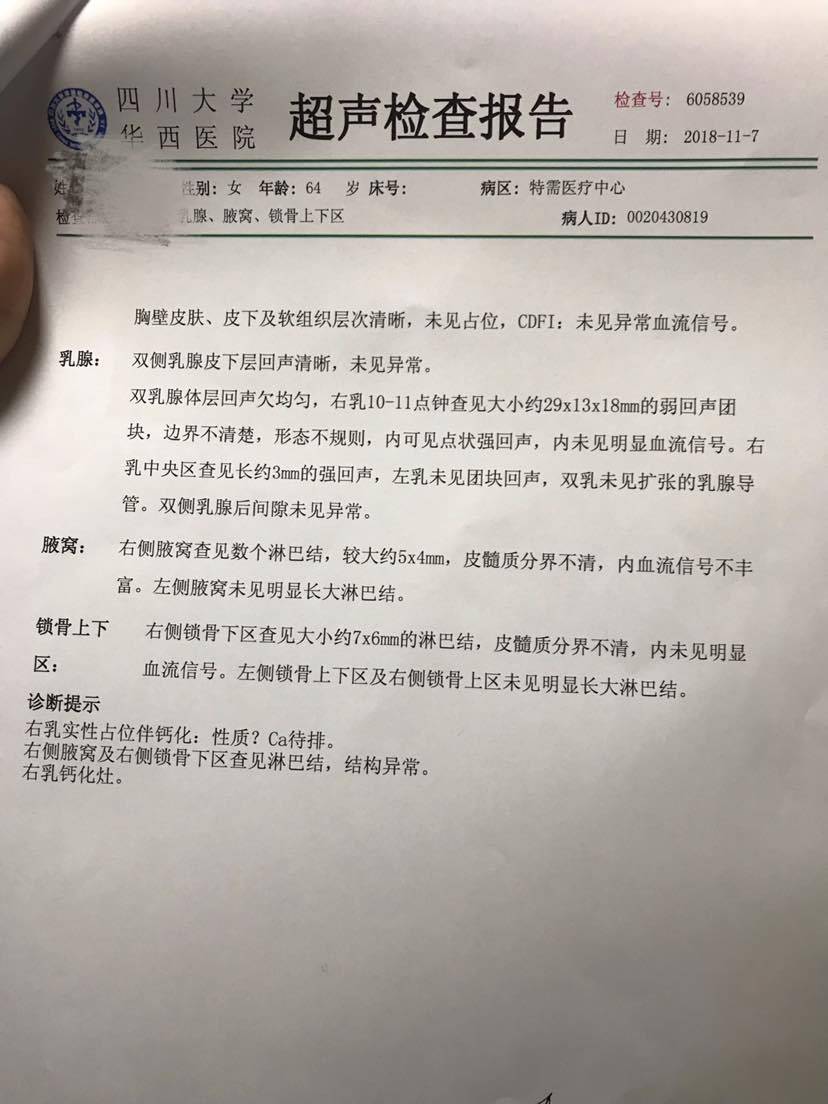

第二家的。有懂的朋友吗?我们也做了最坏的打算,会和我妈妈一起努力的!